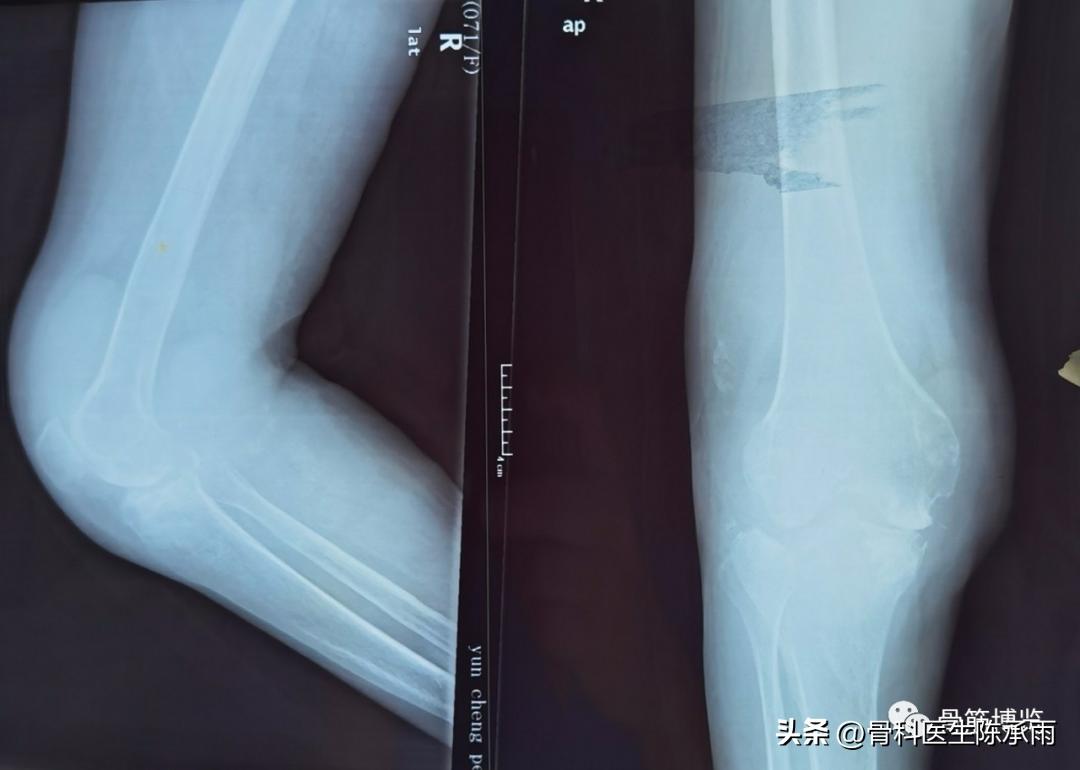

术前影像:

术中情况:关节破坏严重